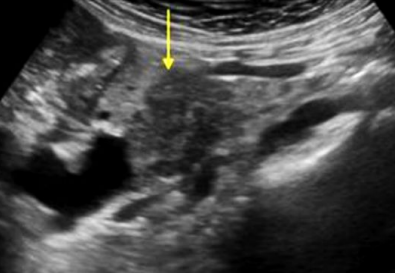

Describe this image

US guided FNA of a pancreatic tumor located in the head of the pancreas (based on landmarks)